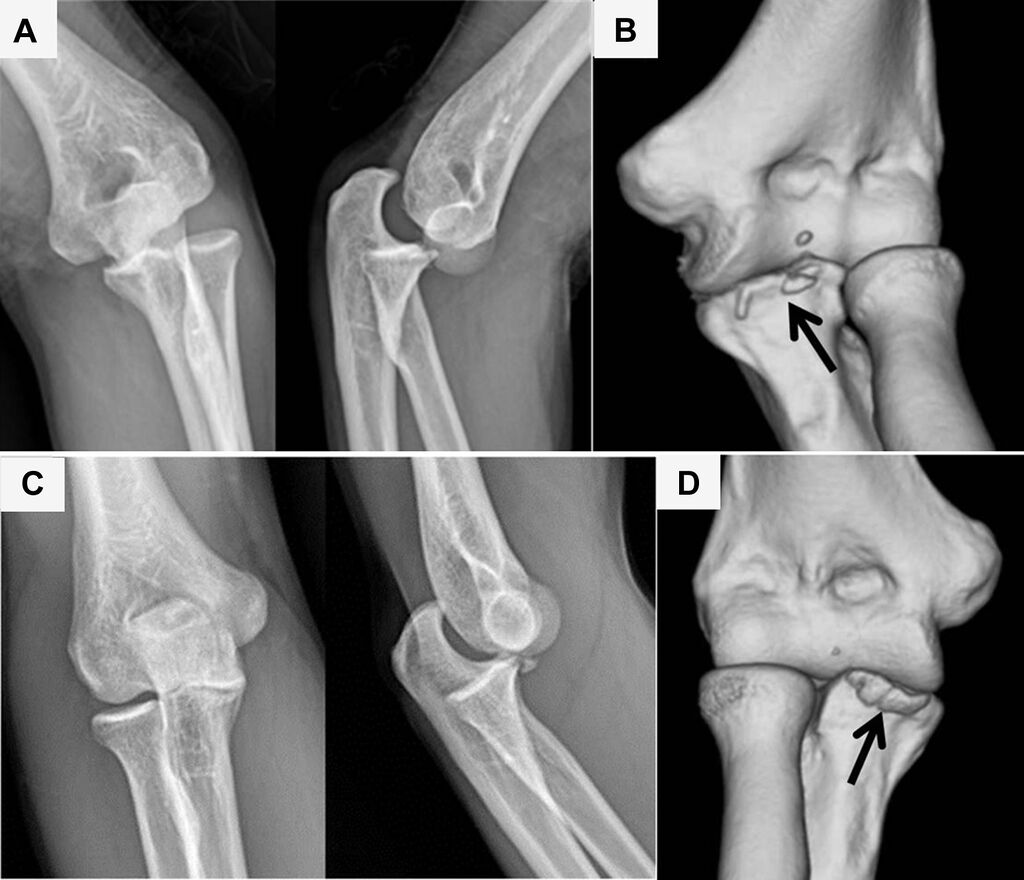

(a) and (b) The circle of Horii. See text for explanation of stage numbers. LUCL, lateral ulnar collateral ligament; MUCL, medial ulnar collateral ligament; PLRI, posterolateral rotatory instability. (Redrawn from O’Driscoll SW, Jupiter JB, King GJ, et al. The unstable elbow.

Posteromedial rotatory instability is a rare elbow injury characterized by abnormal rotational instability of the ulna and radius relative to the humerus, often due to disruption of the medial collateral ligament and supporting structures. It is diagnosed through a combination of

Early identification and appropriate surgery are essential in the management of patients with posteromedial rotatory instability of the elbow to prevent the development of early post-traumatic osteoarthritis. #Surgery #Patients #Osteoarthritis #Trauma https://t.co/eOtcqOQ1Le